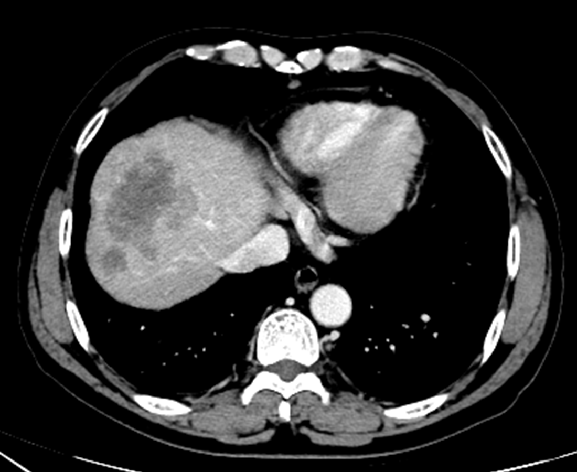

2020.6.8胸腹盆增强CT

升结肠腺癌肝转移 IVA期